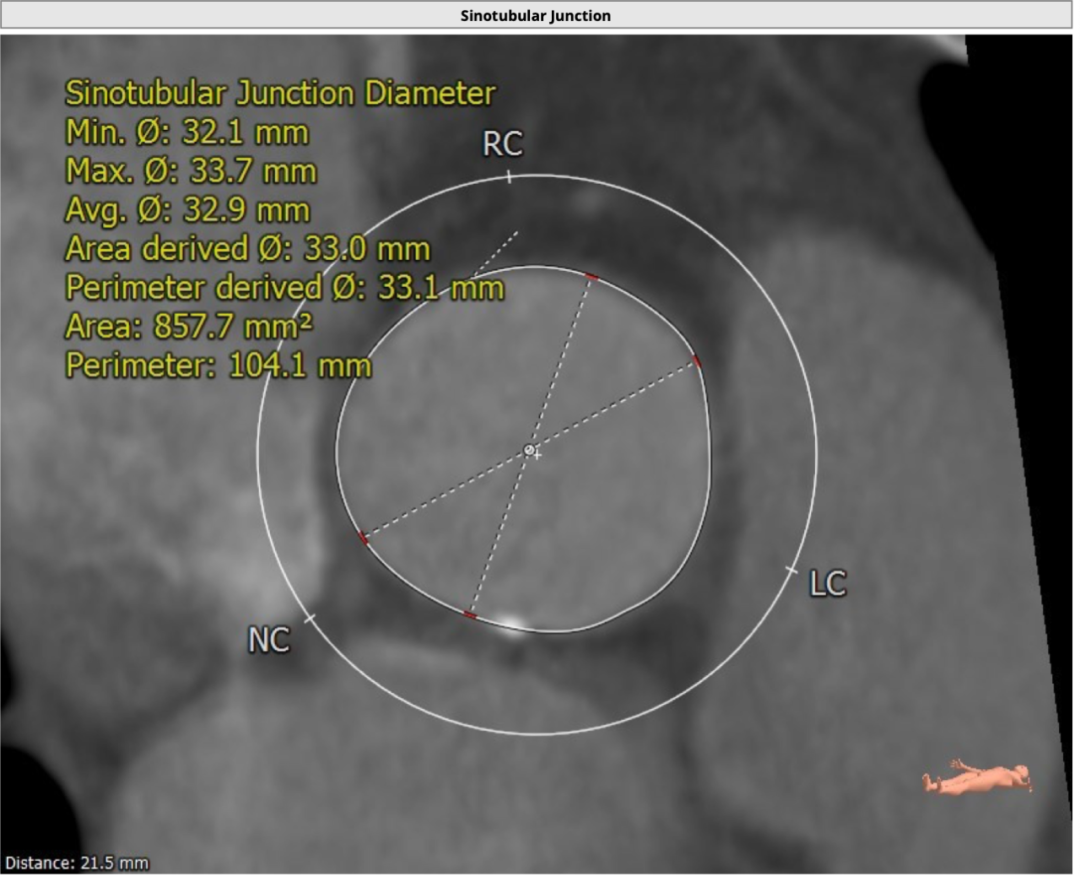

7.png

窦管交界处

该名患者为Type 0型二叶瓣,钙化分布不对称,瓣叶有轻度增厚。瓣环最短径为19.6mm,最长径为25.2mm,平均瓣环直径为22.4mm。左冠开口高度15.6mm,右冠开口高度15.9mm。